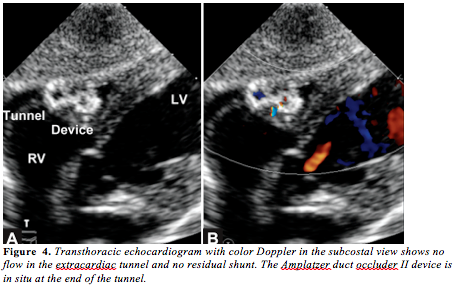

Cardiac catheterization was performed to confirm the diagnosis and to attempt transcatheter closure of the tunnel. Hemodynamic data showed Qp:Qs to be 3:1, with pulmonary artery pressures of 33/17 mm Hg (mean, 22 mm Hg). Aortic pressure was 100/20 mm Hg (mean, 47 mm Hg). Ascending aortogram done in left anterior oblique (LAO) view showed a dilated tortuous tract arising from the right side of the aortic root and draining into the right ventricular outflow tract (RVOT) with an aneurysmally dilated proximal portion (measuring 12 mm) with a narrow opening measuring 6 mm at the RV end (Figure 3A). A Terumo 0.018˝ wire was advanced into the fistulous tract from the aortic end through 4 Fr Cobra catheter into the RV and then into the pulmonary artery. A 4 Fr Cobra catheter was advanced over the wire. The tip of the wire was snared using a 15 mm Goose-neck snare advanced into the left pulmonary artery through the right femoral vein. The standard arteriovenous (AV) loop was made. Over this wire, a 7 Fr Cook shuttle delivery sheath was advanced into the fistula from the RV end with great difficulty. A futile attempt was made to introduce a 10 x 8 Amplatzer duct occluder (ADO). The check angiogram showed that the device was not in the tunnel. As there was an acute bend at the RV end of the tunnel, the large delivery sheath with the bulky ADO was not entering the tunnel. Hence, we decided to close the tunnel with the ADO II, which can be introduced from the aortic end without an AV loop as it has low profile.

The tunnel was recrossed from the aortic end with a 0.018˝ Terumo wire; over that, a 5 Fr Terumo catheter was introduced into the pulmonary artery and then exchanged with a 0.035˝ J-tip regular wire. A 5 Fr Cook shuttle sheath was advanced over the wire. A 6 x 6 ADO II device was loaded and advanced easily into the delivery sheath. The distal disc of the device was released in the pulmonary artery and the whole system was pulled to the opening of the tunnel in the RVOT. The position of the distal retention disc was checked both by TTE and angiography. Then, the rest of the device was deployed in the aneurysmally dilated portion of the tunnel. The device was released after the check angiogram showed good position of the device with no residual shunt (Figure 3B). After the procedure, on clinical examination, pulse was 100/min with normal volume, blood pressure was 100/80 mm Hg, and no murmur was heard on auscultation. The TTE with color Doppler in the subcostal view showed the device in situ with no residual shunt (Figure 4). The infant had an uneventful postprocedure stay in the hospital and is normal on follow-up after 9 months. The ECG remained normal.